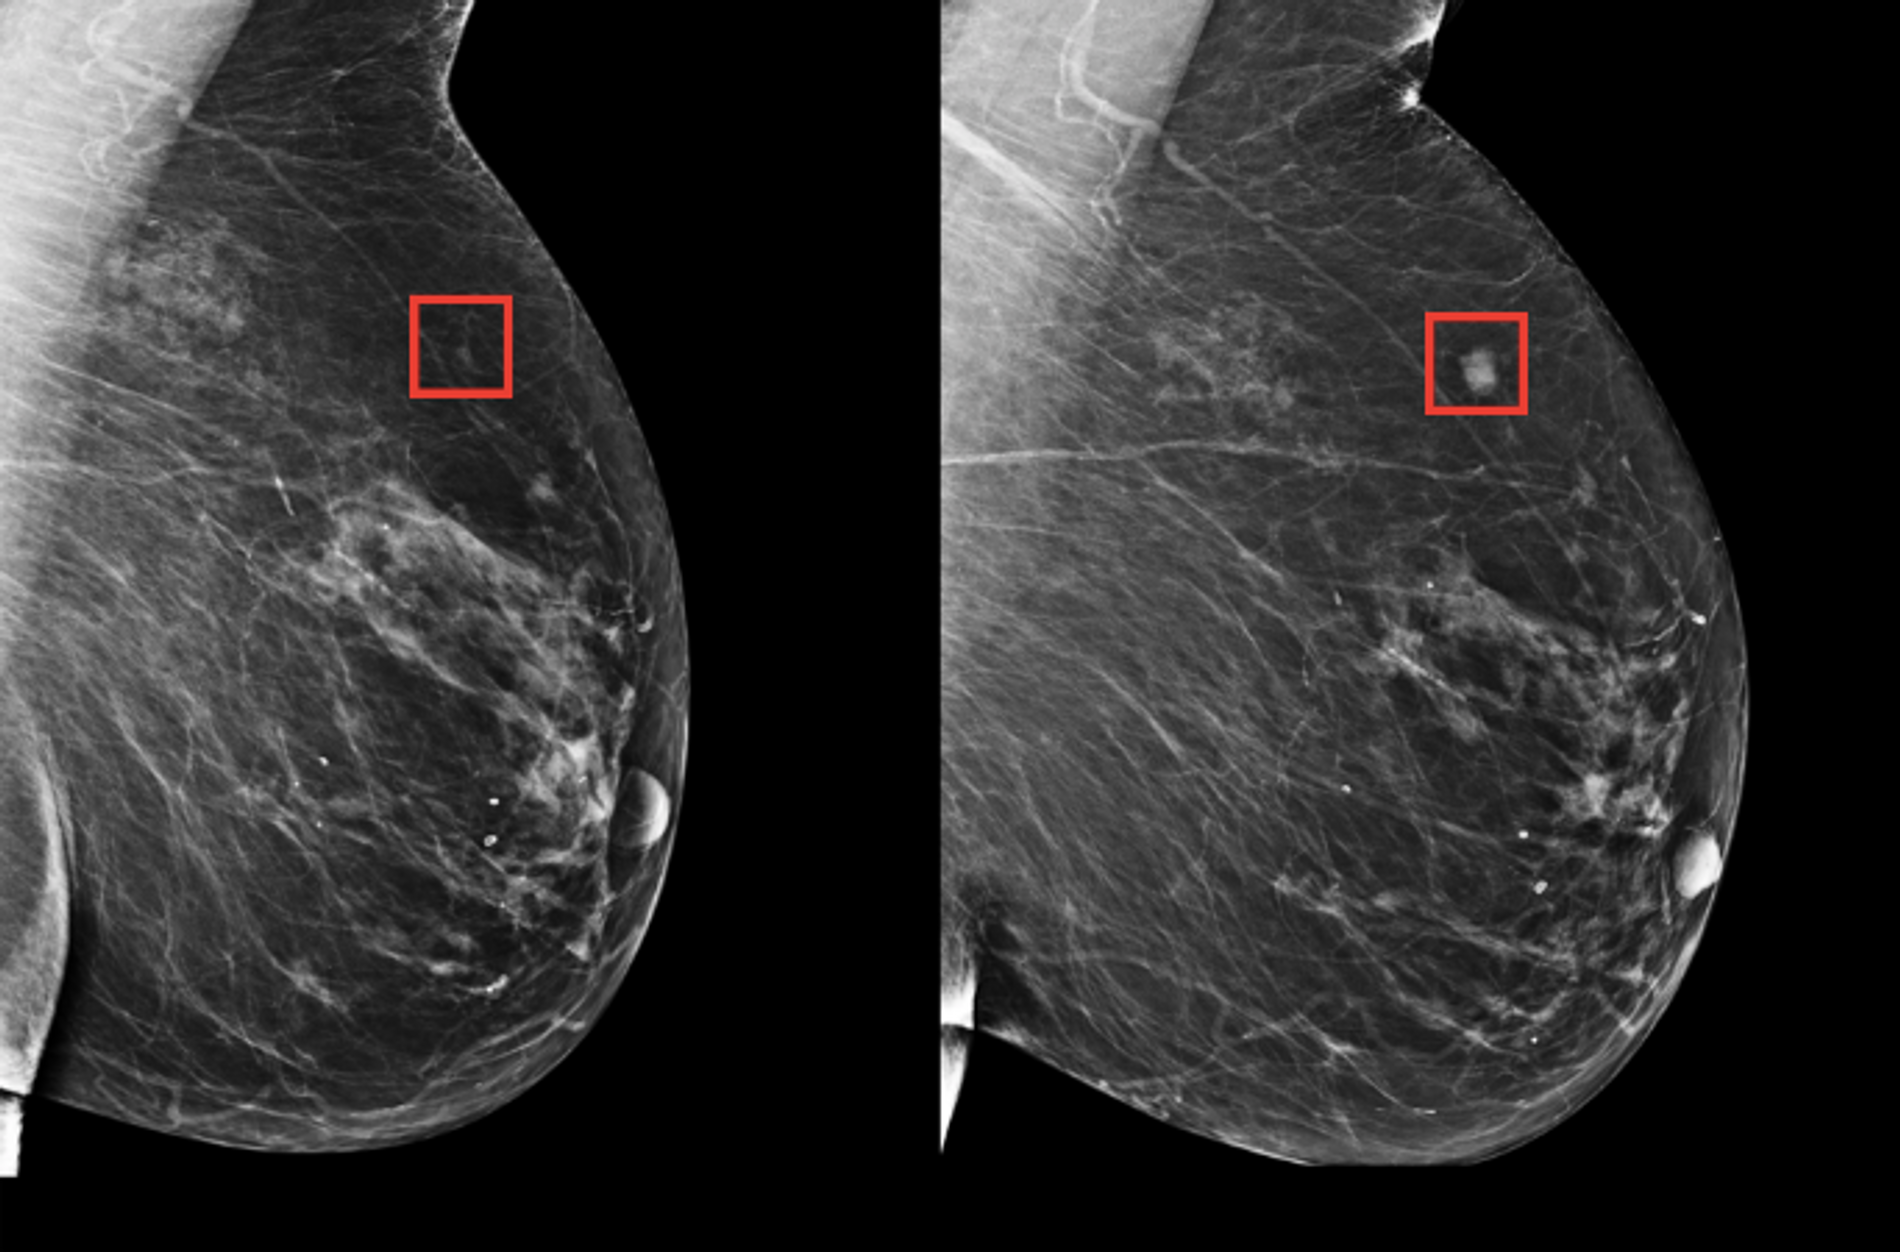

Un programa de Inteligencia Artificial (IA) parece capaz de reducir la carga de trabajo de los radiólogos en la detección del cáncer de mama, según los primeros datos de un estudio publicado el miércoles, aunque es demasiado pronto para concluir sobre su eficacia.

Realizado en Suecia y publicado en The Lancet Oncology, este estudio concluye también que no hay riesgo de que los radiólogos utilicen software de inteligencia artificial (IA) para orientar mejor sus análisis.

Los investigadores dividieron a unas 80.000 mujeres en dos grupos de tamaño similar.

Todas ellas realizaron una mamografía, pero el primer grupo se cribó de forma convencional, es decir con la mirada de dos radiólogos independientes, mientras que los datos del segundo fueron examinados primero por una IA y luego por un solo radiólogo.

El grupo asistido por la IA no registró peores resultados e incluso se detectó un número un poco más elevado de cánceres.